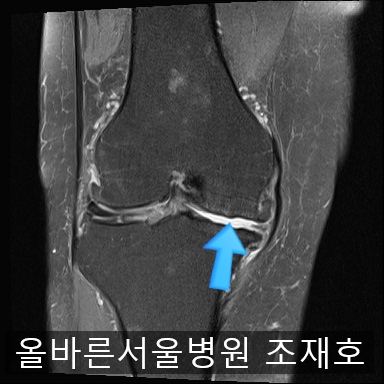

为了掌握具体情况拍了MRI。

髌骨关节虽有炎症,但仍保留相当一部分软骨。

内侧关节软骨几乎不见,软骨板也受损严重。软骨损伤部位充满关节液。

软骨板损伤严重

虽然前方十字韧带粘液样变性,但稳定性无异常

后方十字韧带无明显异常。